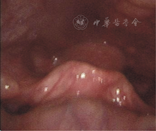

23例LTGDC患儿经直接喉镜或电子喉镜检查发现,在舌根与会厌之间出现新生物,基底位于舌根后方,居中12例,正中偏左7例,正中偏右4例。11例呈类圆形、灰白色半透明,表面光滑可见血管纹(图1),12例舌根后方呈球面隆起,颜色与周围组织一致,其中3例首次电子喉镜检查时曾被漏诊,经喉CT检查后再次检查确认。